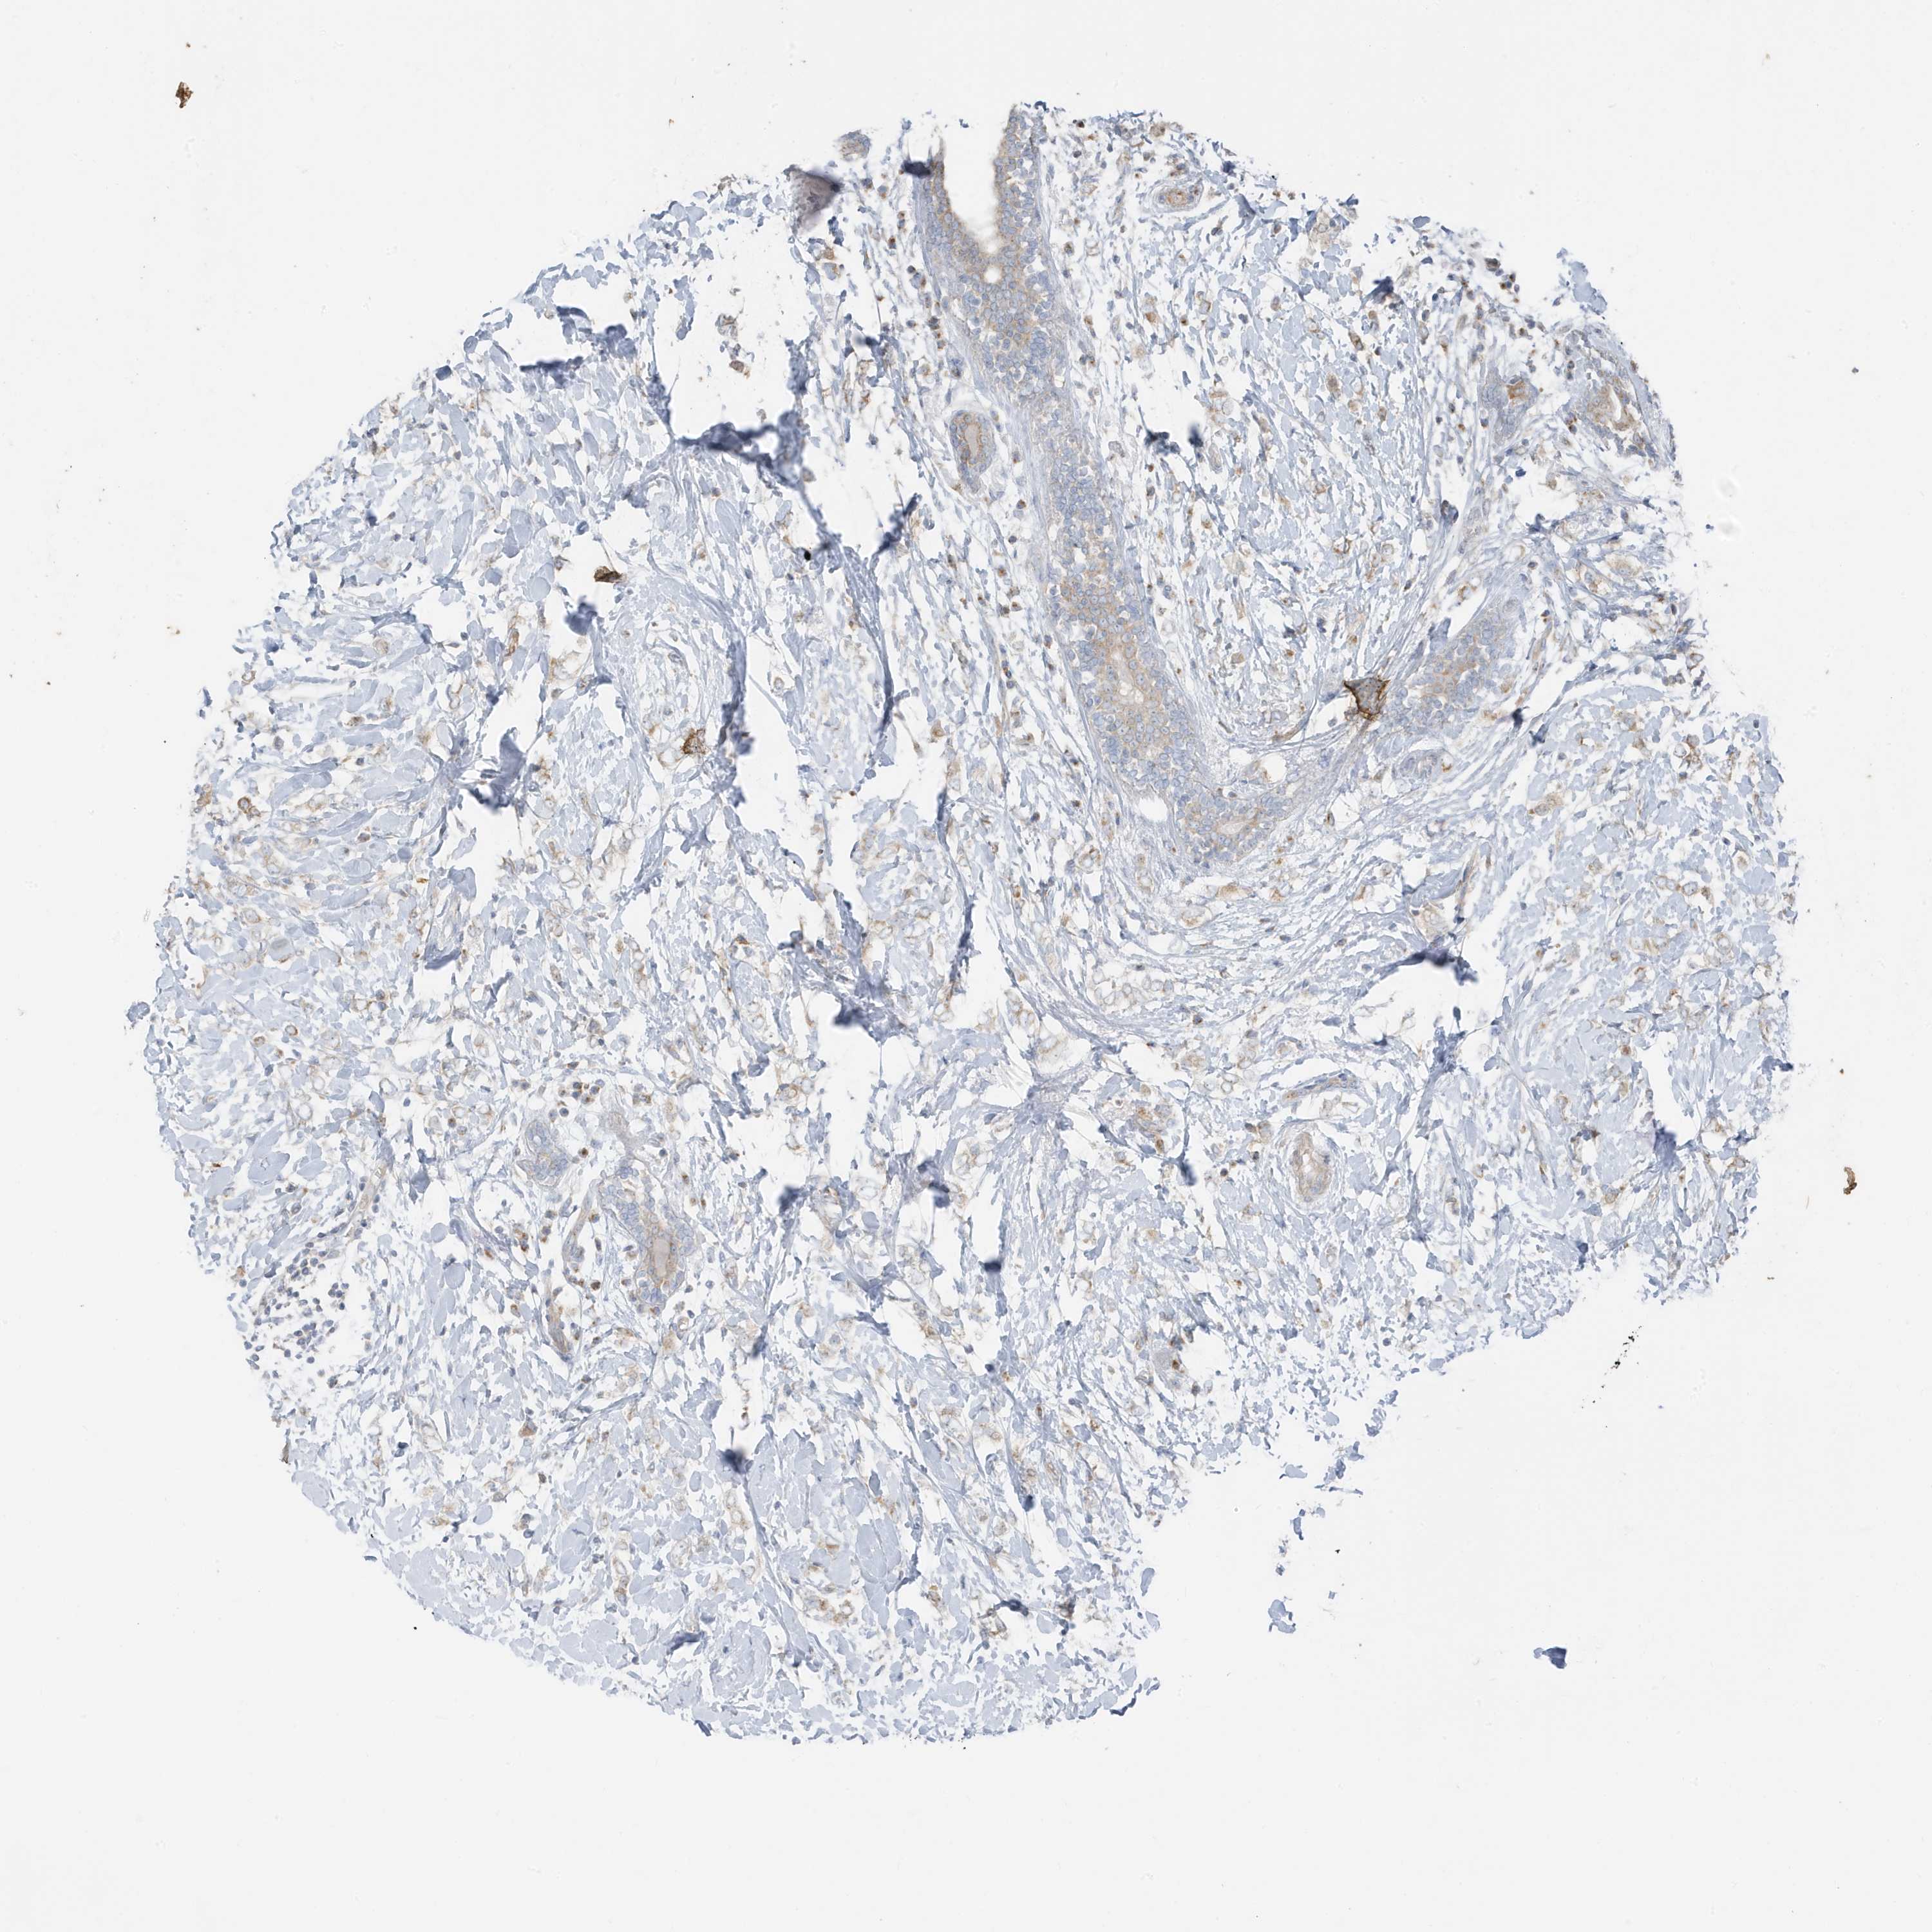

CANCER BREAST CANCER Show tissue menu

BRCA TCGA BRCA VALIDATION PROTEIN EXPRESSION